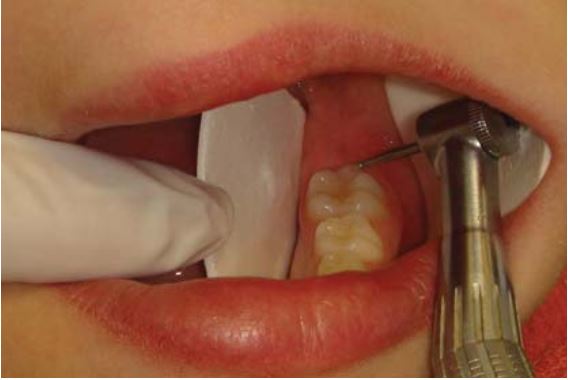

Mở rộng hố rãnh bằng mũi tròn #2 trước khi bơm sealant đôi khi được khuyến cáo để tăng bề mặt kết dính hoặc loại bỏ mô răng sâu (H9.6).